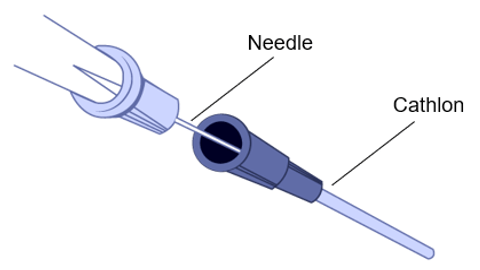

If the patient has an IV in place when they arrive to the CT suite, try to inject the contrast media using a different injection site since the injection will be under pressure rather than slow perfusion. This will help to avoid any local complications at the injection site.

Tingling in the Arm

Prickling or tingling are the two terms used by patients. The contrast comes “under pressure” in the vein. If the tip of the cathlon is close to the wall of the vein it causes stimulation. This feeling is accentuated for patients who have had chemotherapy as their veins have become more sensitive.

Risk of Extravasation

IV infiltration is one of the most common problems that can occur when fluid infuses into the tissues surrounding the venipuncture site. This sometimes happens when the tip of the catheter slips out of the vein, the catheter passes through the wall of the vein, or the blood vessel wall allows part of the fluid to infuse into the surrounding tissue.

Extravasation occurs when there is accidental infiltration of a vesicant that can cause blistering or chemotherapeutic drugs into the surrounding IV site. Vesicants can cause tissue destruction and/or blistering. Irritants can result in pain at the IV site and along the vein and may or may not cause inflammation. Extravasation can result in tissue sloughing, pain, loss of mobility in the extremity and infection.

The extravasation of contrast agents is an unwanted occurrence that can cause irreversible local injuries.

Extravasation of CT scan contrast media into upper extremity subcutaneous tissue is a relatively frequent complication of injection. Contrast extravasation one hour after injection showing a large area in the biceps compartment. Elevation and massage can help with the pain as well as warm compresses.